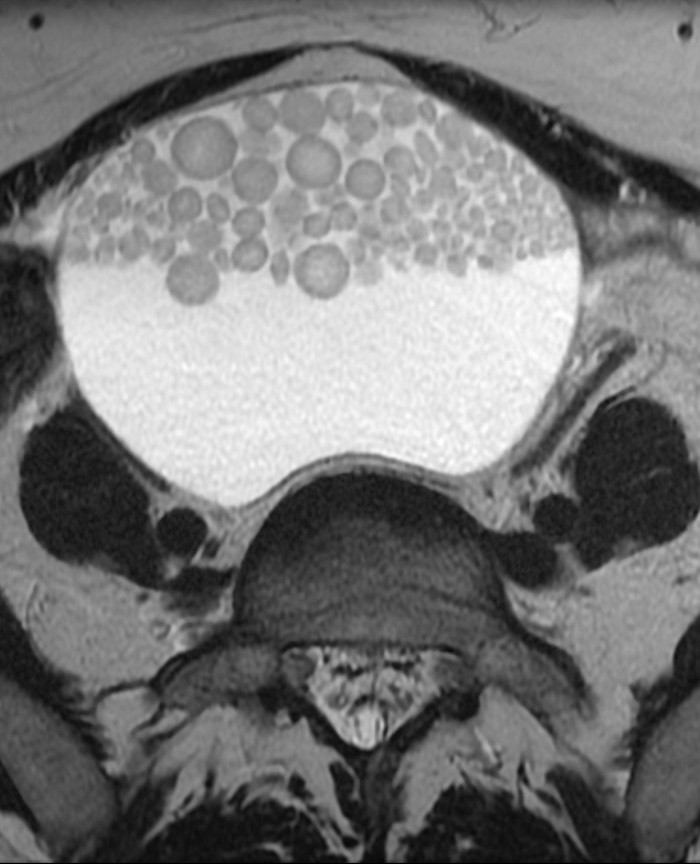

En kvinne tidlig i 40-årene var henvist til MR-undersøkelse av lille bekken for karakterisering av ovariecyster. To cyster på ca. 5 – 6 cm inneholdt fett. Aksialt T2-vektet bilde (se bilde) viste en større cyste på 15 cm som inneholdt væske og multiple antideklivt beliggende, solide kuler. Disse var av varierende størrelse, men ellers ganske ensartede. Slike kuler kan – når de er til stede – ha et karakteristisk utseende ved ultralyd (floating intracystic balls) og regnes som patognomoniske for dermoidcyster (2). De består vesentlig av talg og keratin. Sentralt finnes gjerne et nidus, eksempelvis et hårstrå. Det er nærliggende å sammenlikne utviklingen av disse kulene med danningen av en perle i en musling.